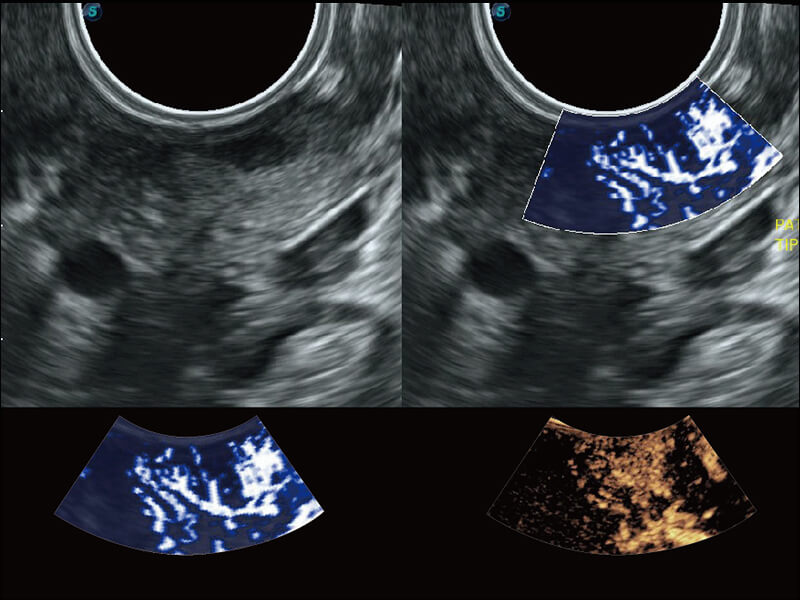

超宽频带技术,为容积成像带来优质的二维图像基础,为您呈现丰富的结构细节,栩栩如生地展示宝宝的宫内形态以及各种组织的立体结构。